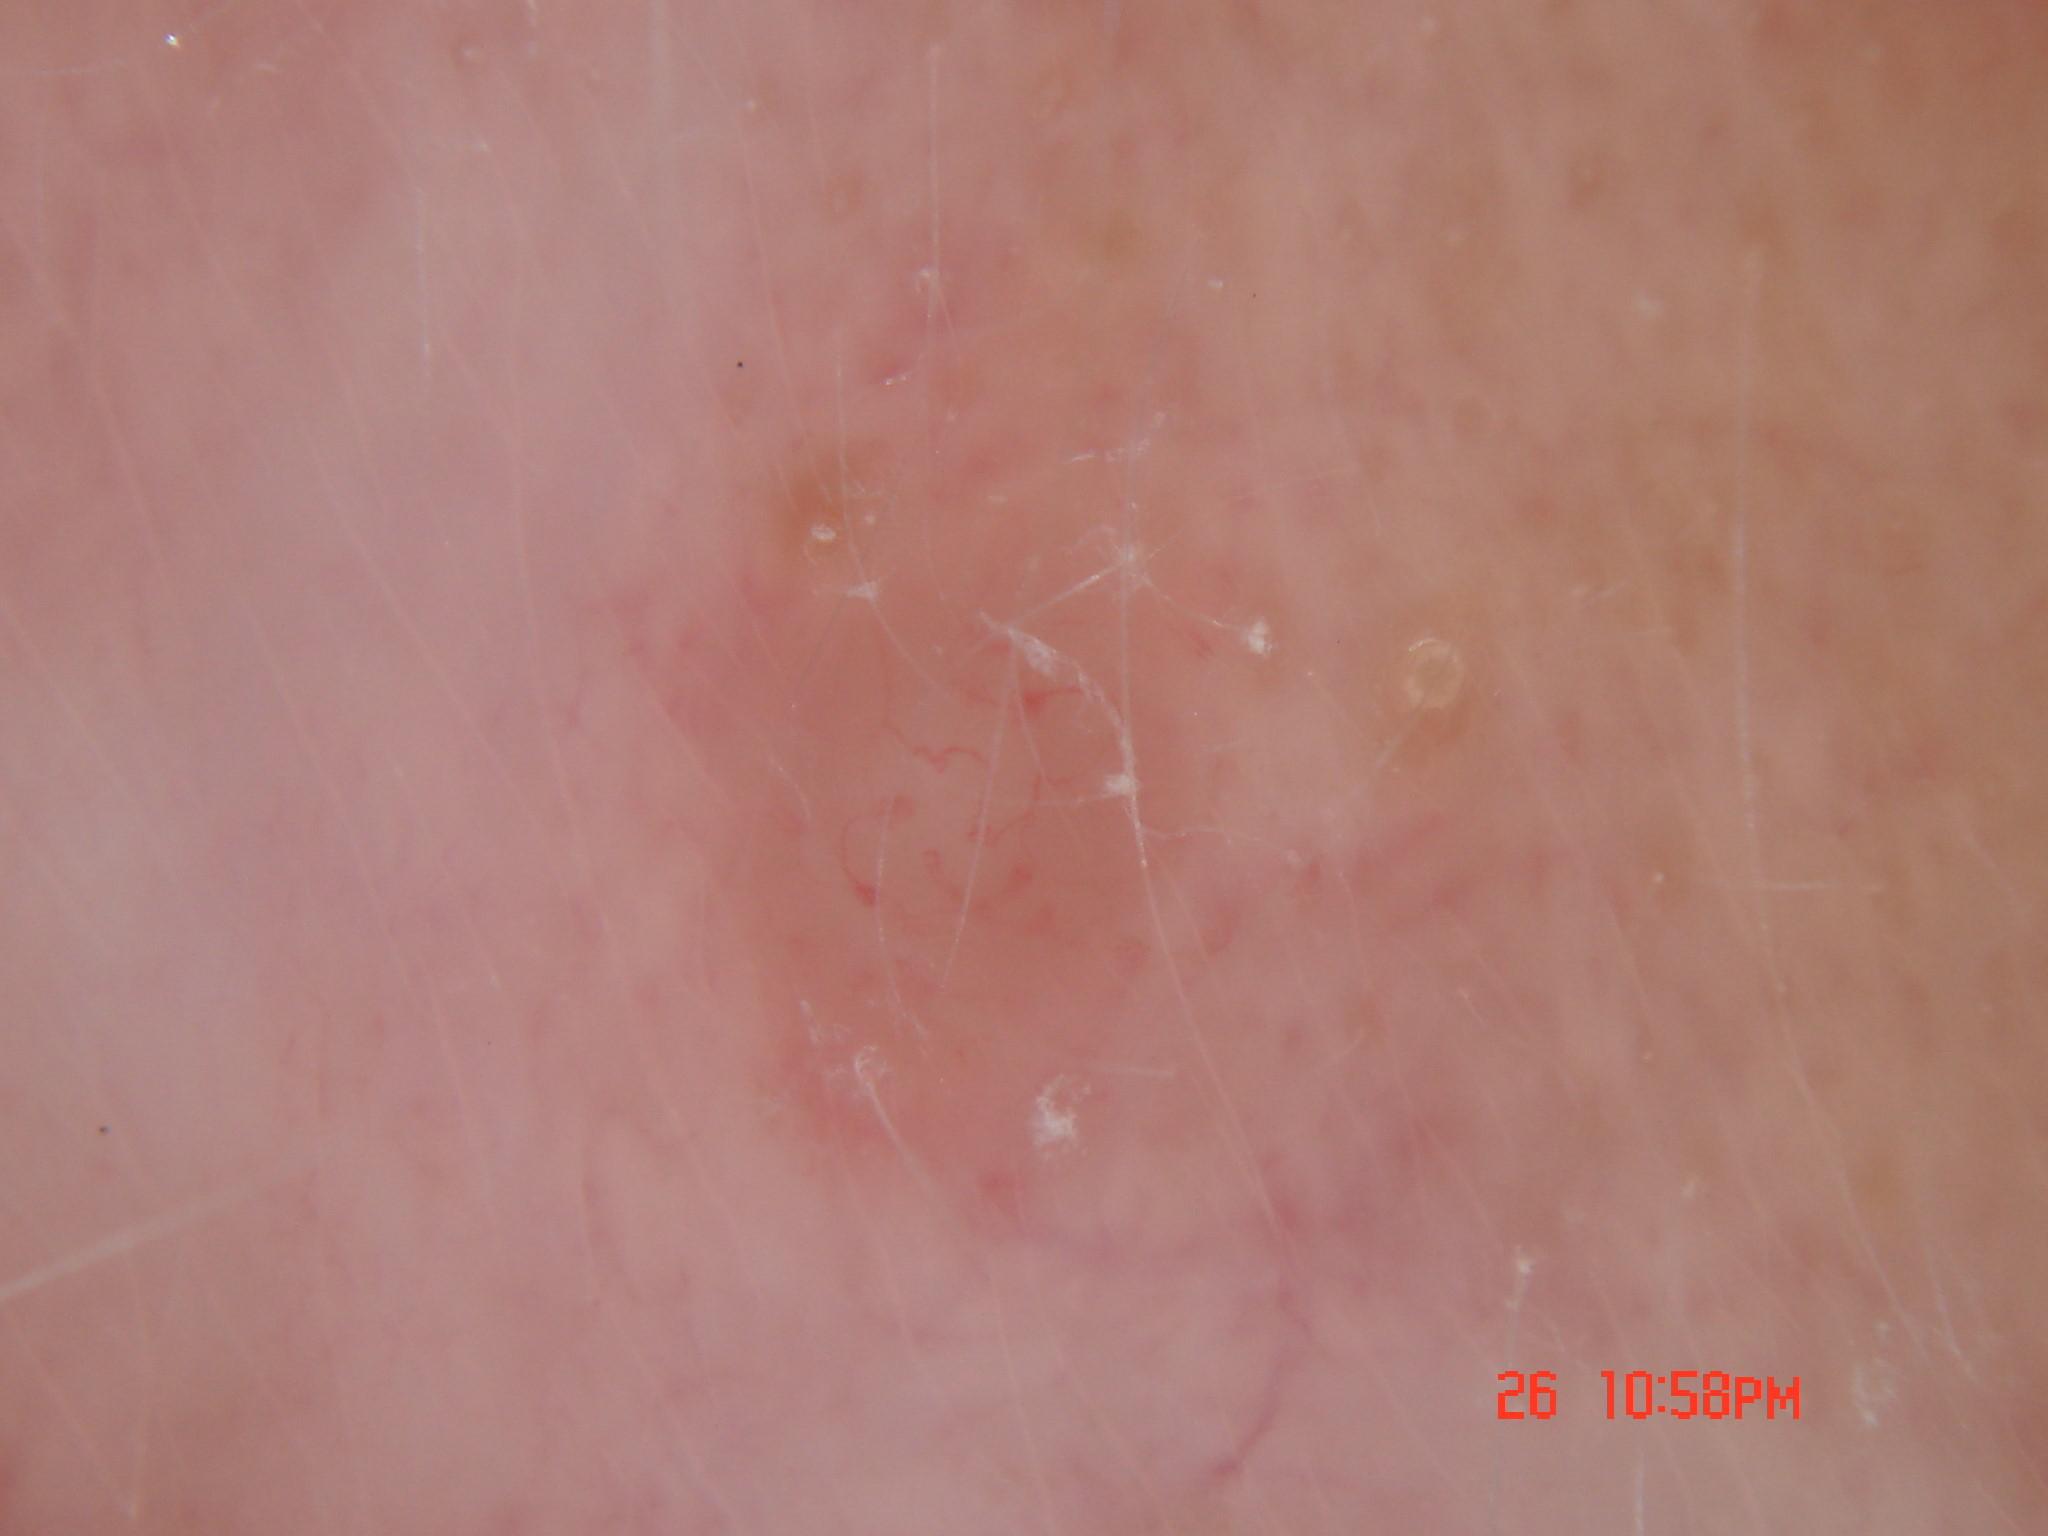

{

"age_approx": 50,

"anatom_site_general": "lower extremity",

"concomitant_biopsy": true,

"dermoscopic_type": "contact non-polarized",

"diagnosis_1": "Benign",

"diagnosis_2": "Benign melanocytic proliferations",

"diagnosis_3": "Nevus",

"diagnosis_4": "Nevus, NOS, Junctional",

"diagnosis_confirm_type": "histopathology",

"family_hx_mm": false,

"image_type": "dermoscopic",

"melanocytic": true,

"patient_id": "IP_4103931",

"personal_hx_mm": false,

"sex": "female"

}